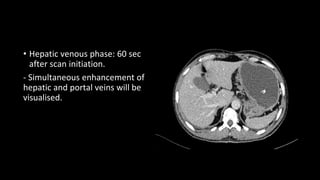

• Hepatic venous phase: 60 sec

after scan initiation.

- Simultaneous enhancement of

hepatic and portal veins will be

visualised.